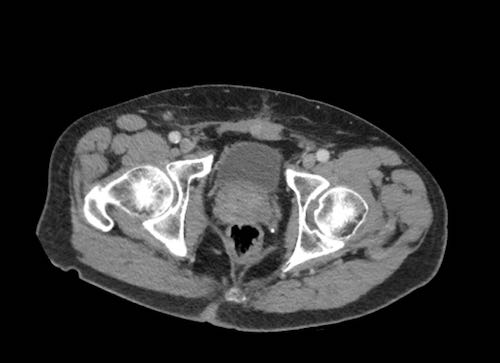

Cuộn xem ảnh CT

Ca lâm sàng 1

Cuộn qua các lát cắt.

Bạn có thể phát hiện tất cả các tổn thương cấy ghép phúc mạc không?

Bệnh nhân này đã được phẫu thuật và toàn bộ phúc mạc được ghi nhận phủ kín bởi các tổn thương u dạng kê.